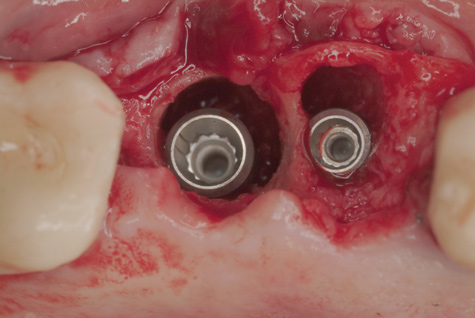

(3.) Two implants removed with two separate techniques. The narrow implant had an abutment that was easily removed, making it possible to engage with a reverse torque device. The wider implant contained a fractured abutment screw and required removal with a trephine. Its wider platform dictated that the trephine fit over this portion, and the osseointegrated bone can be seen attached to the explanted fixture.

Figure 3